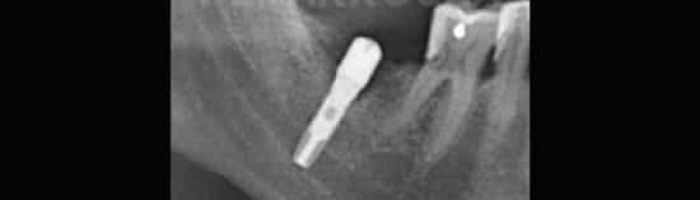

También se considera una cirugía bucal la cirugía periapical. Esta cirugía se realiza en casos de fracaso de una endodoncia. Antes de extraer un diente endodonciado que vuelve a presentar infección en muchas ocasiones puede realizarse una cirugía periapical para acceder a eliminar directamente la infección, y dar una nueva oportunidad a este diente.

María Ros nos cuenta su experiencia tras someterse a un tratamiento de cirugía periapical en nuestra clínica odontológica en Valencia.

“Gracias al Dr. Peñarrocha decidí hacerme la cirugía periapical y a raíz de ahí fue todo fenomenal. En IDIM te sientes como en casa”.